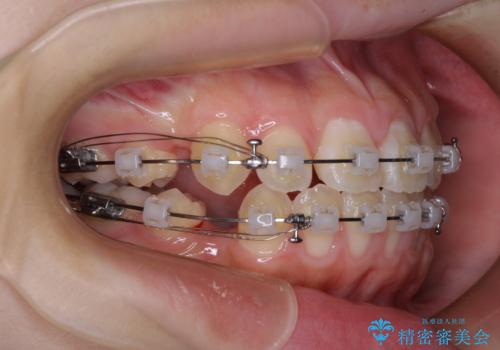

- クリアブラケット

舌の突出癖により上下前歯は接触できず、更には前方に押し出されて出っ歯になっている状態でした。

上下左右の第一小臼歯4本を抜歯し、ワイヤー装置での抜歯矯正を行っていくのですが、原因である舌の突出癖を改善しないことには治療がうまく進められないため、舌のトレーニングを徹底するよう指導していくこととしました。